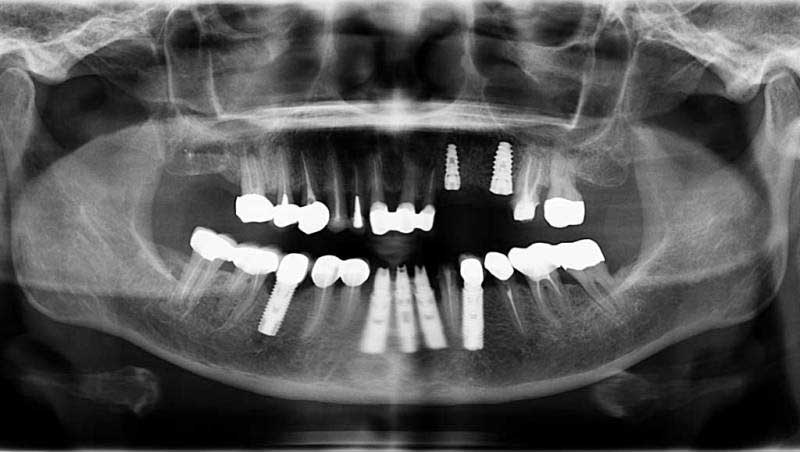

案例1

植牙併發症處理前